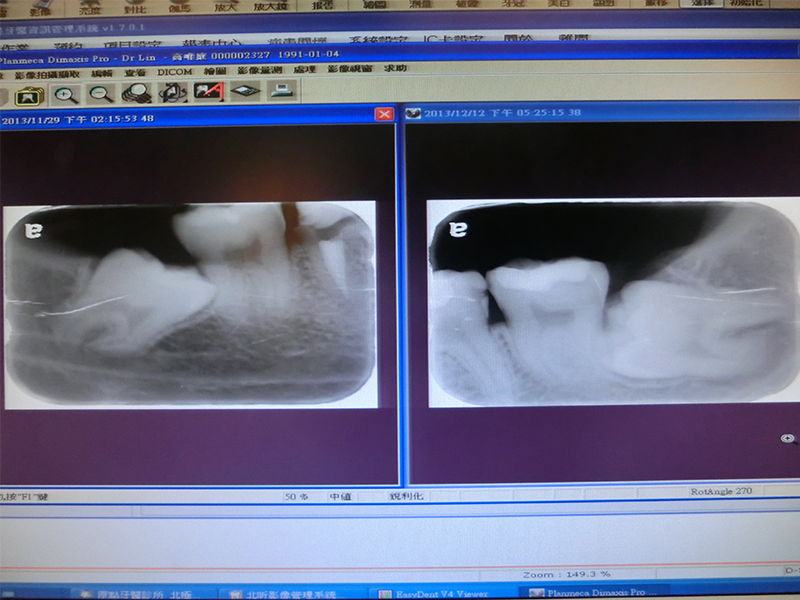

首先先來看看我的牙齒X光照片XD

看不太懂沒關係貼心的我幫各位標示了一下~

▲左邊簡直是水平生長啊!!!他超困難的,是第二次才拔掉,一開始先拔的是右邊~